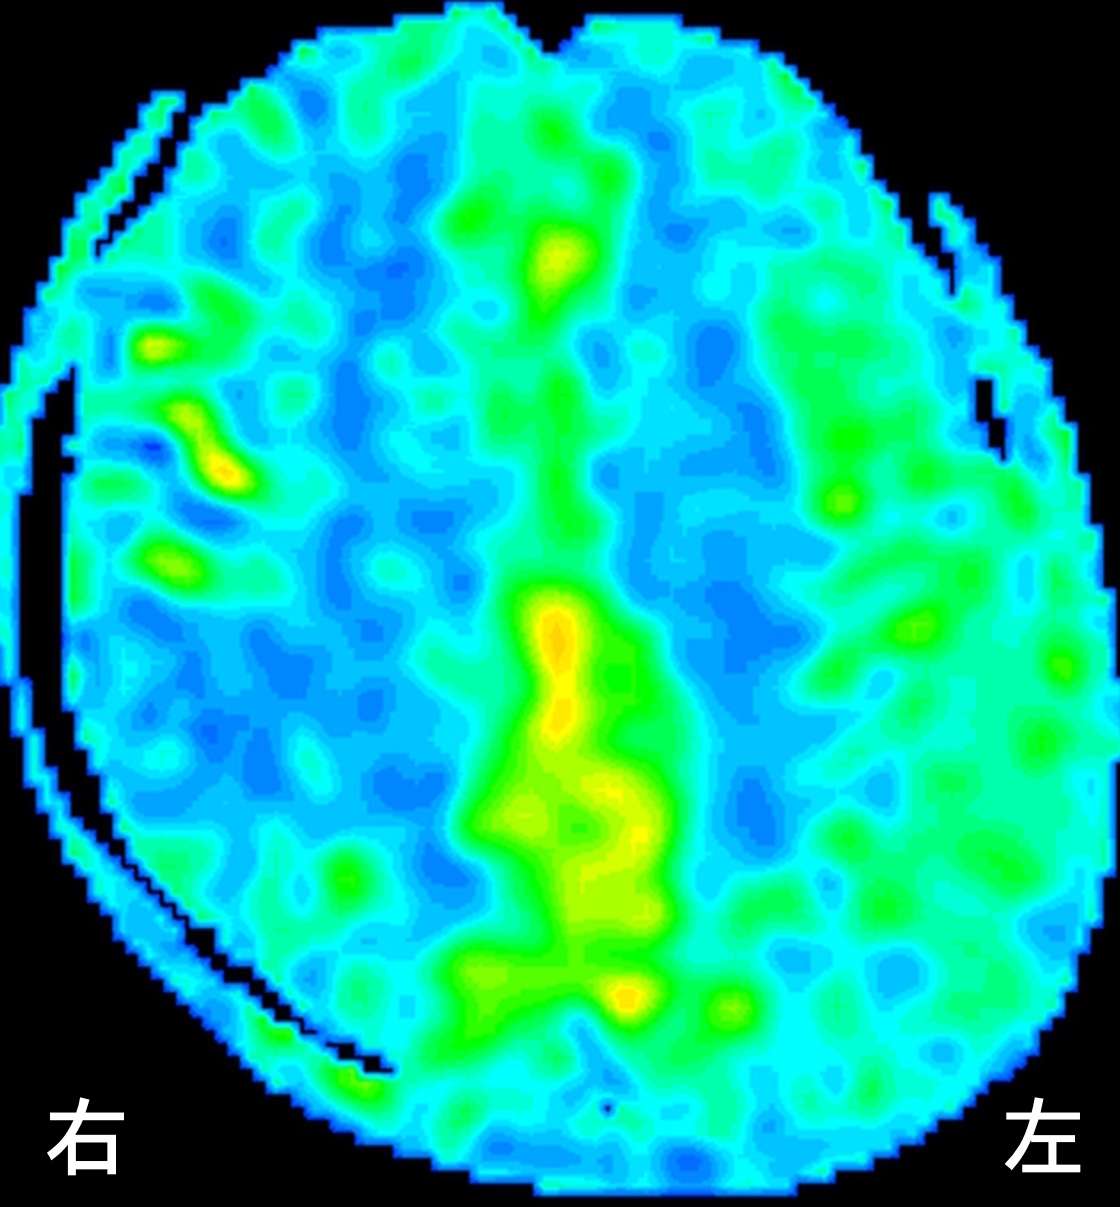

ASL中期

徐々に血流が補われていく状態がうかがえます。